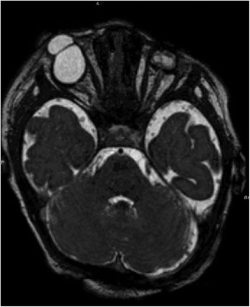

MRI revealed microphthalmos in the left ocular globe and a coloboma-like structure in the right in a female infant with Fraser syndrome.